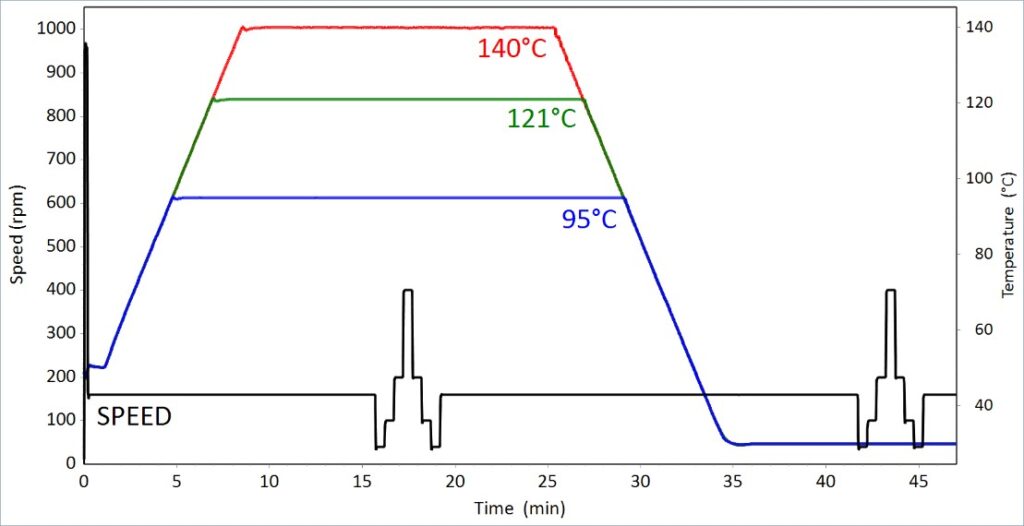

Echo image of right ventricular apex (RVA) pacemaker, pressure

Anatomy for right ventricular lead implantation Herzschrittmachertherapie + Elektrophysiologie

Final position of the wire positioned in the apex of the right

Nonapical Right Ventricular Pacing Is Associated with Less Tricuspid Valve Interference and Long-Term Progress of Tricuspid Regurgitation - ScienceDirect

A proposed technique for right ventricular septal pacing

Adverse effects of right ventricular pacing on cardiac function: prevalence, prevention and treatment with physiologic pacing - ScienceDirect

The short term influence of right ventricular pacing burden on echocardiographic and spiroergometric parameters in patients with preserved left ventricular ejection fraction, BMC Cardiovascular Disorders

Strategies and Pacemaker Algorithms for Avoidance of Unnecessary Right Ventricular Stimulation